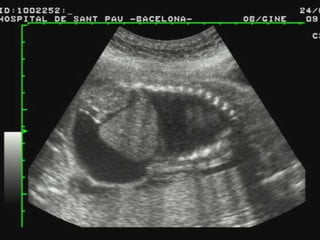

ASCITIS

•DESDE PEQUEÑAS COLECCIONES.

•ACUMULACIONES MAYORES.

DERRAME PLEURALY O

PERICARDICO.

DERRAME PLEURAL

HALLAZGOS ECOGRÁFICOS: ASCITIS,

DERRAME PLEURAL, EDEMA SUBCUTÁNEO,

EDEMA PLACENTARIO.